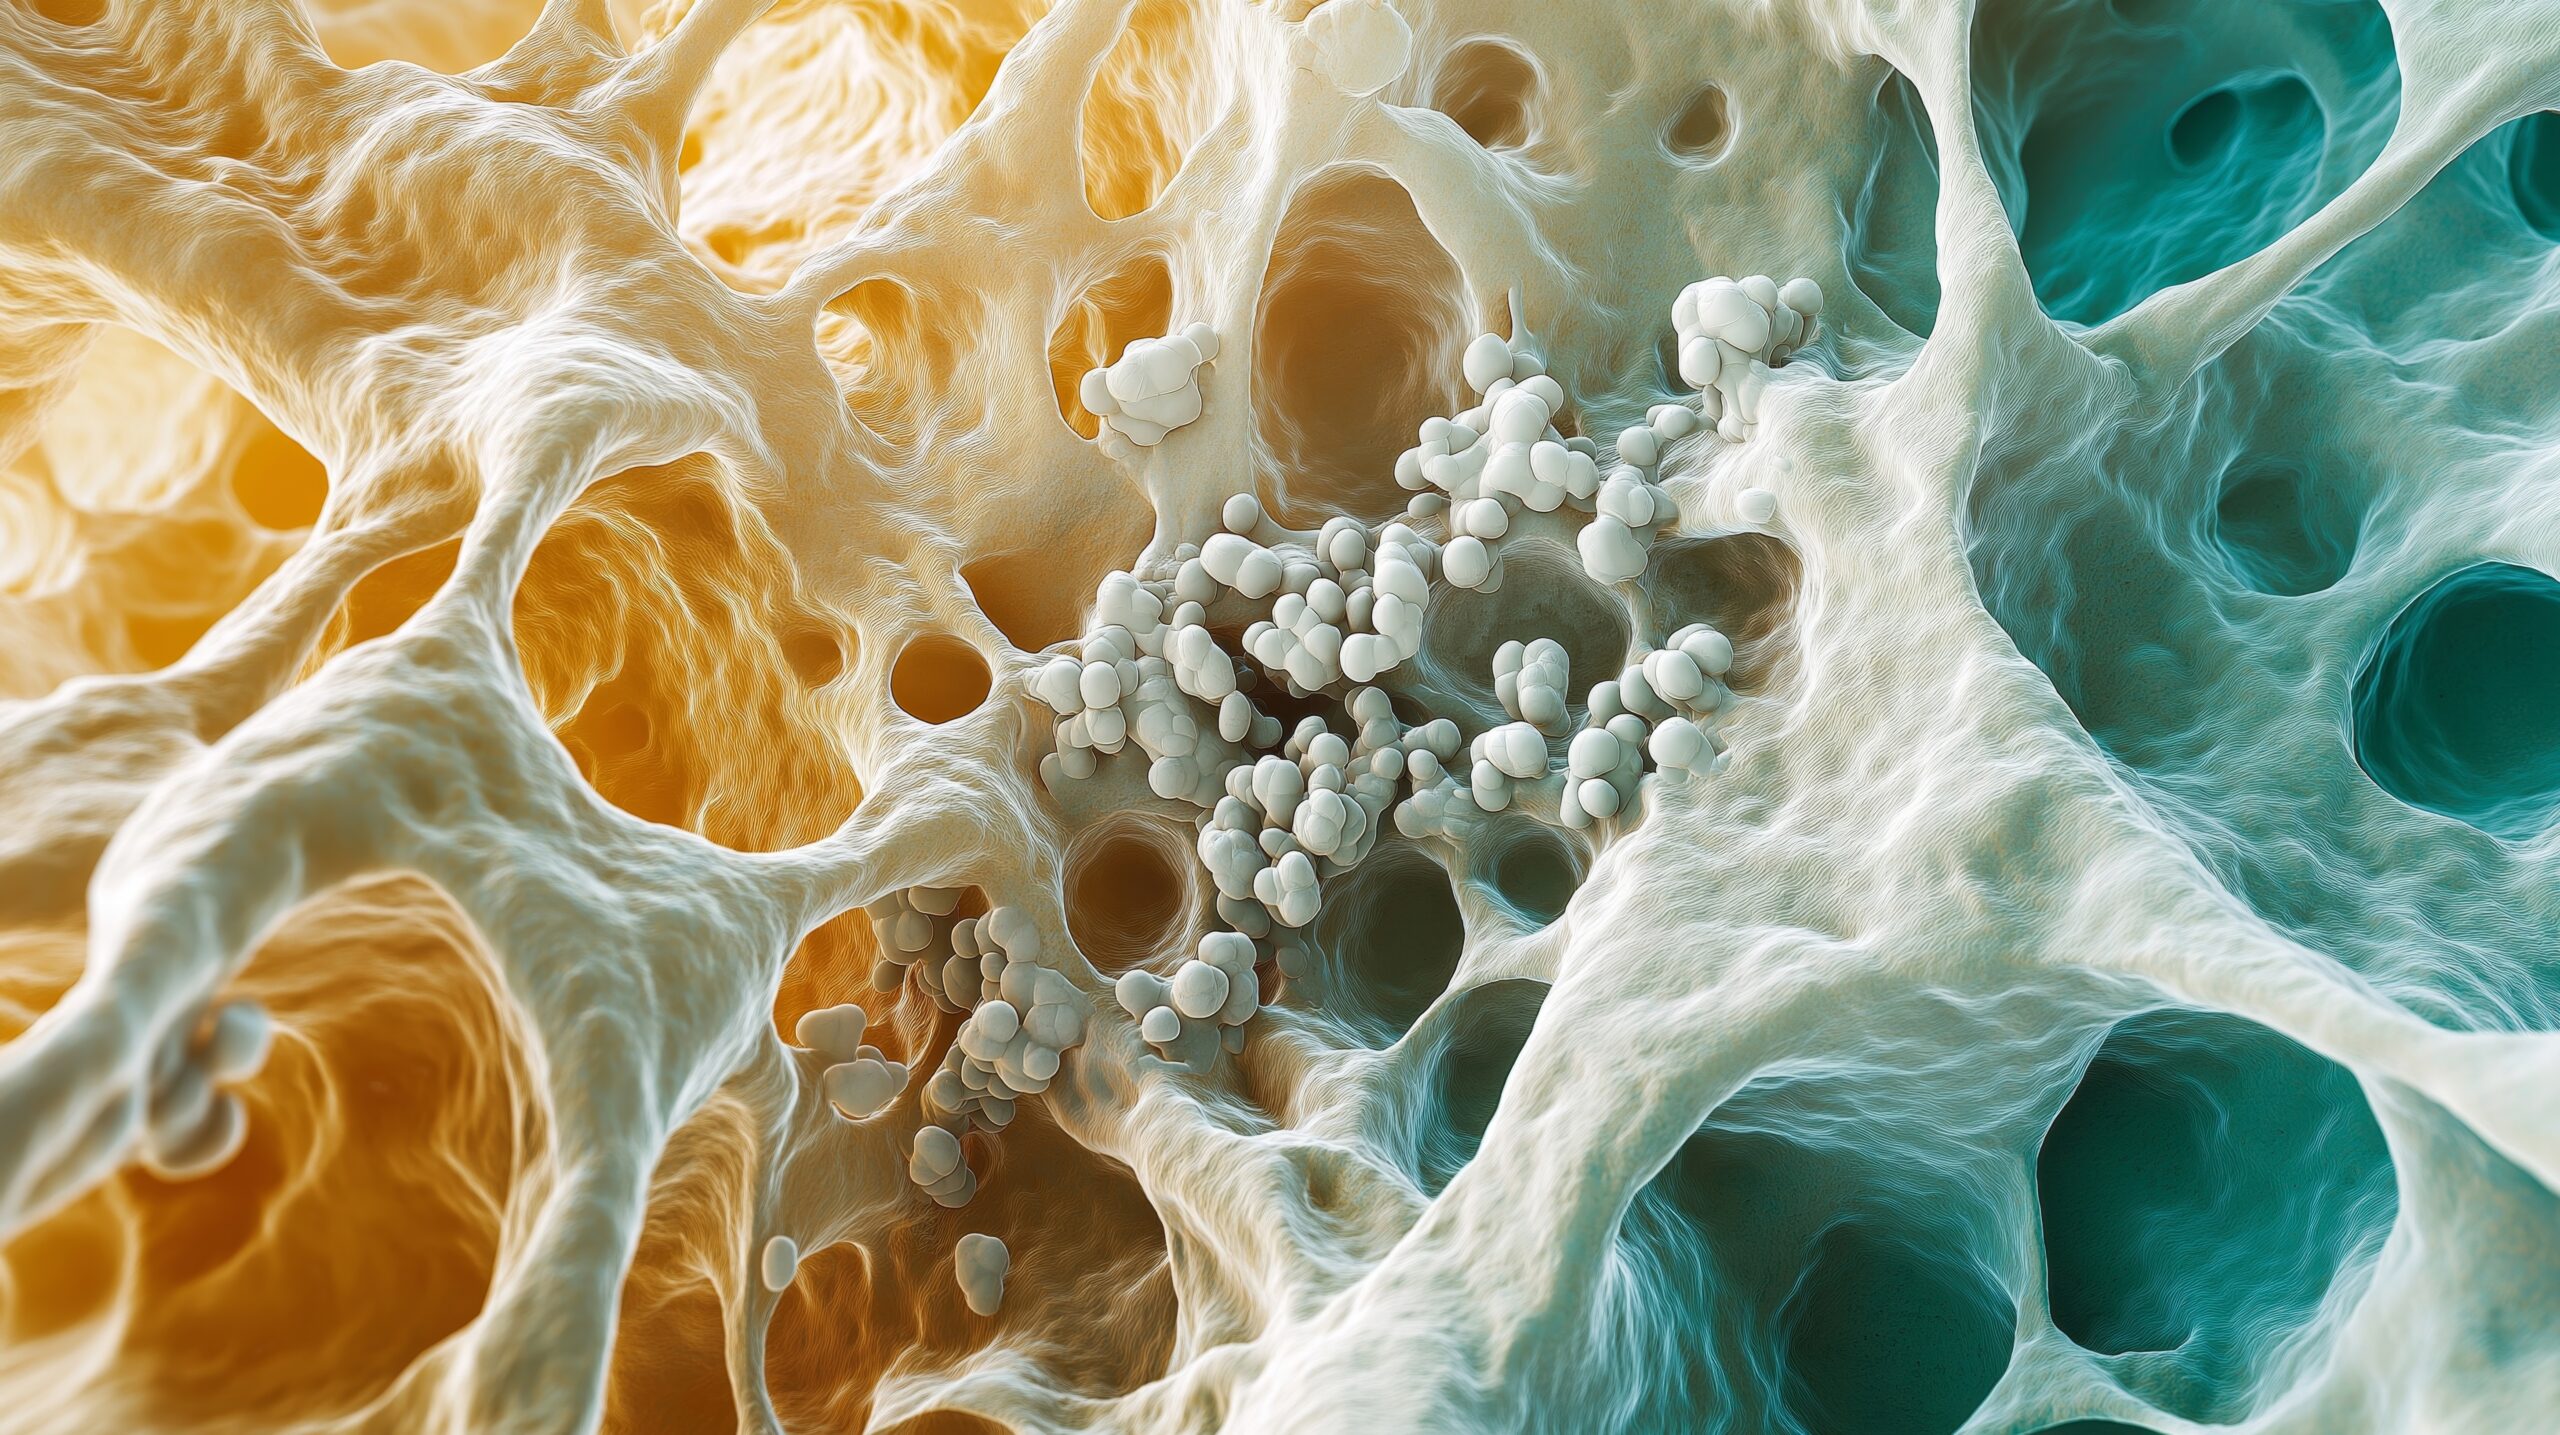

Mesenchymal stem cells (MSCs) are multipotent progenitor cells found in connective tissues. They have the unique ability to migrate to damaged tissues, differentiate into various cell types (osteoblasts, chondrocytes, adipocytes, etc.), and evade immune rejection. These properties make them one of the most widely studied cell types in regenerative medicine and cellular therapy.

MSCs can be derived from multiple tissues throughout the body. The most commonly used sources include:

In the laboratory, cells are isolated from these sources, cultured under sterile conditions, and expanded to produce sufficient quantities suitable for therapeutic use.

MSCs are multipotent stem cells found in connective tissues. They can migrate to damaged areas, differentiate into various cell types, and evade immune rejection.